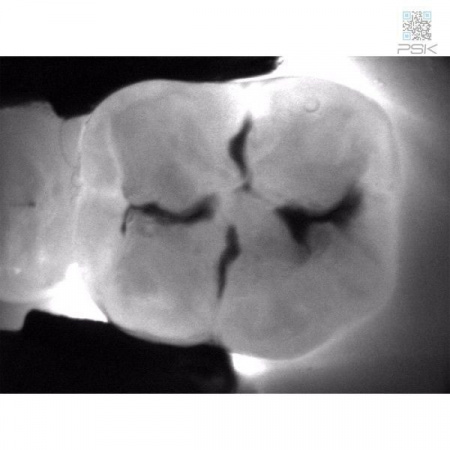

KaVo DIAGNOcam дает Вам полную уверенность в точности результата диагностики. С его помощью Вы сможете обнаружить кариозные поражения на самом раннем этапе развития.KaVo DIAGNOcam позволяет визуализировать их на аппроксимальных и окклюзионных поверхностях зубов и обеспечивает проведение диагностики вторичного кариеса (при небольшом размере пломбы).

Весь секрет заключается в технологии DIFOTI™ за счет генерируемого прибором трансилюминационного (трансиллюминация - яркое сквозное освещение) лазерного излучения в нерентгеновском диапазоне волн. Если объяснять это простым языком, то это – излучение, занимающее диапазон между видимым светом и рентгеновским диапазоном, которое проходит сквозь твердые ткани зуба, при этом области, не пропускающие свет (например, области кариозного поражения) отображаются в виде затемненных на общем фоне участков.

Цифровая видеокамера фиксирует результат и передает изображение на экран в режиме реального времени.

Рентгенограммы и снимки, полученные с помощью KaVo DIAGNOcam, относятся к методам диагностики, прекрасно дополняющим друг друга. С помощью рентгенологической диагностики Вы в дальнейшем сможете беспрепятственно проверить и дополнить данные KaVo DIAGNOcam, исключив часть рентгеновского излучения для пациента. На снимках отчетливо визуализируются структуры коронковой части зуба, располагающиеся выше уровня десневого края. Таким образом, становится возможным раннее распознавание кариеса и проведение профилактического, малоинвазивного лечения. Ваши пациенты будут в восторге!Удобный и информативный план лечения для Ваших пациентов